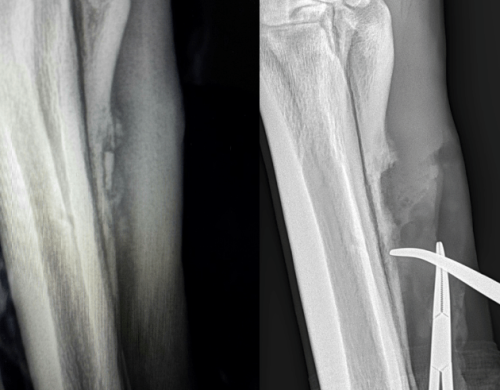

A pre-surgical consultation is important so you fully understand the reason your horse requires surgery and to establish what steps are necessary prior to and after the procedure. During this consultation, results of lameness examination and diagnostic imaging are discussed so it is important to provide these to the surgeon ahead of time if they were performed by your regular vet. Sometimes one or more of these studies will need to be repeated, if sufficient time has elapsed between the original study and the surgery date.